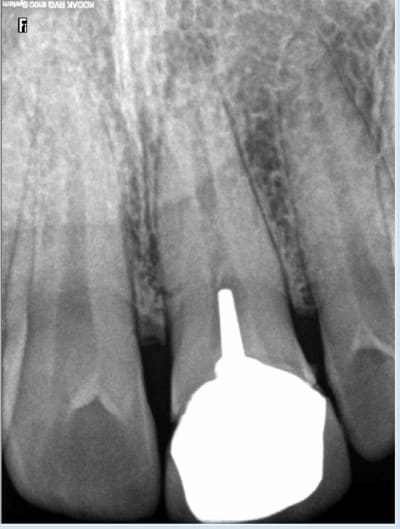

Pennwell.web.400 - Eugenol

Ce qui est intéressant dans ta radio Hoksai c'est de voir que la racine où un certain effort a été fait pour aléser , obturer c'est celle qui est la plus atteinte , la pseudo pulpo aurait mieux marché on dirait .